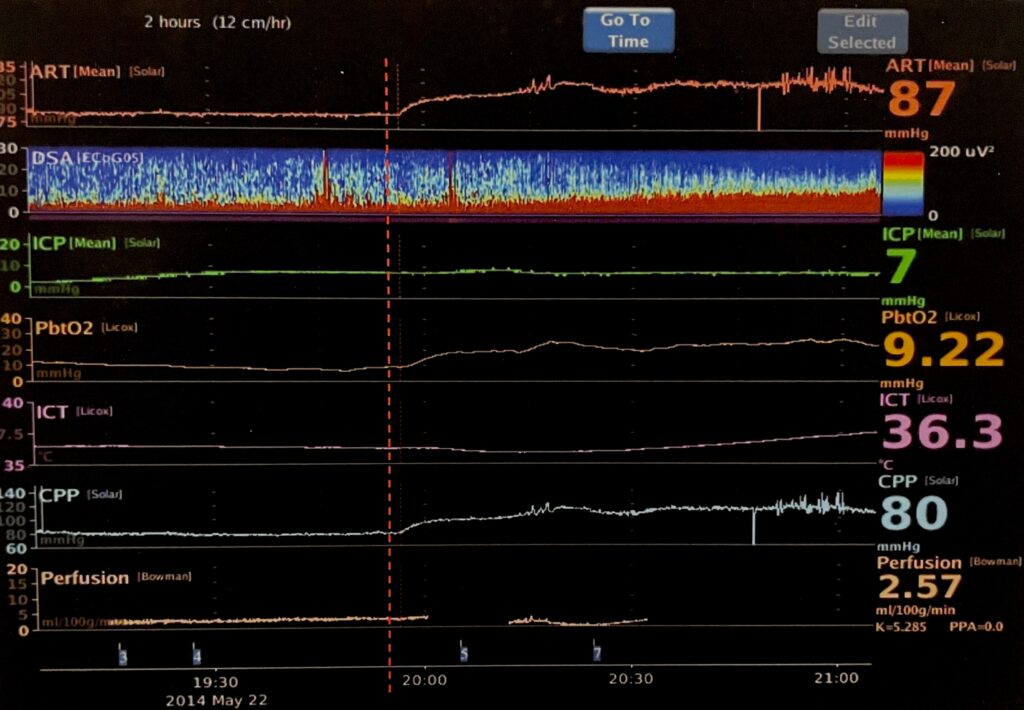

The CNS Monitor was the first device to collect high-resolution data from different neuromonitors and time synchronize it to a common clock, allowing correlations to be visualized.

Synchronized data shows the action of a vasopressor (given at red line) on other trends.